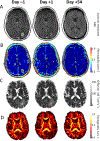

Despite major therapeutic advances in the management of patients with breast cancer, central nervous system (CNS) metastases remain an intractable problem, particularly in patients with metastatic HER2-positive and triple-negative breast cancer. As systemic therapies to treat extracranial disease improve, some patients are surviving longer, and the frequency of CNS involvement seems to be increasing. Furthermore, in the early-stage setting, the CNS remains a potential sanctuary site for relapse. This review highlights advances in the development of biologically relevant preclinical models, including the development of brain-tropic cell lines for testing of agents to prevent and treat brain metastases, and summarizes our current understanding of the biology of CNS relapse. From a clinical perspective, a variety of therapeutic approaches are discussed, including methods to improve drug delivery, novel cytotoxic agents, and targeted therapies. Challenges in current trial design and endpoints are reviewed. Finally, we discuss promising new directions, including novel trial designs, correlative imaging techniques, and enhanced translational opportunities.